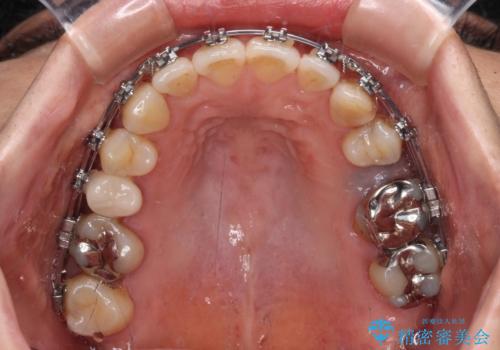

- 矯正装置

- メタルブラケット

- 飛び出した上顎前歯と正中のズレを気にして来院された患者様です。

上顎正中が右側にずれていたので、むし歯が酷く抜歯が必要な左側臼歯を抜歯して正中を改善することとしました。

右上小臼歯は銀歯が装着されており、ワイヤー矯正の装置が装着できないため、事前に仮歯に変えてから矯正治療を行い、その後オールセラミッククラウンにて補綴治療を行いました。